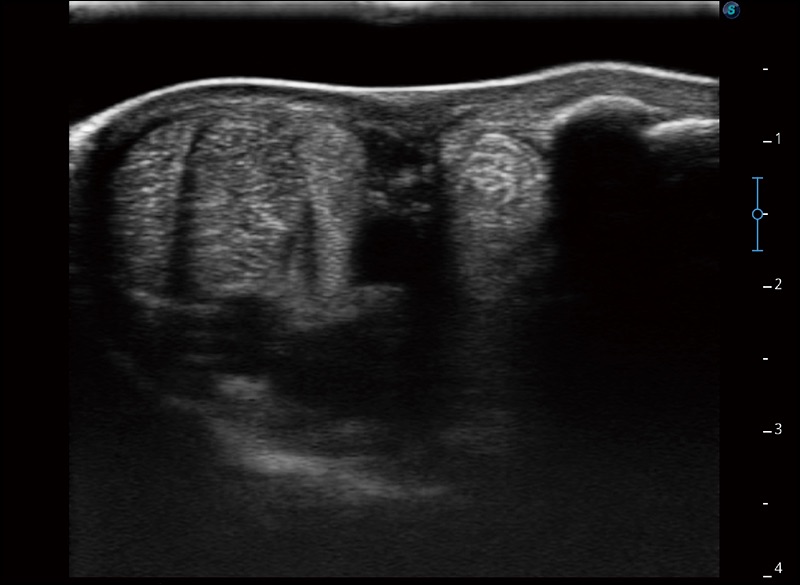

空间复合成像

优化不同角度的图像

实时宽景成像

可实时观察感兴趣区域和病变位置